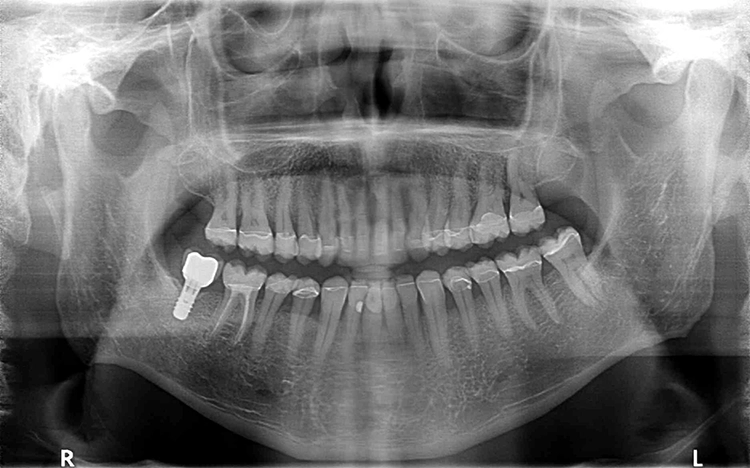

Die OPT-Aufnahmen zeigen keinen Anhalt auf nicht zahnverursachte Prozesse, dafür einen leichten bis mäßigen horizontalen und vertikalen Knochenabbau im Oberkieferseitenzahnbereich und generalisiert im Unterkiefer sowie einen periimplantären Knochenabbau in Regio 47 (Abb. 2). Die Zahnhartsubstanzdefekte imponieren als halbmondförmige Aufhellungen im Okklusalbereich von den Zähnen 37, 35, 34, 44 und 45. Es zeigen sich ebenso Aufhellungen im Approximalbereich mesial 24, distal 43 und mesial 37 (Abb. 4 und 5).

Parodontale Gesundheit bei Attachmentverlust, Bruxismus, Erosion. Abbildung 1 sowie 6 bis 9 zeigen den Anfangsbefund als intraoralen Fotostatus.*